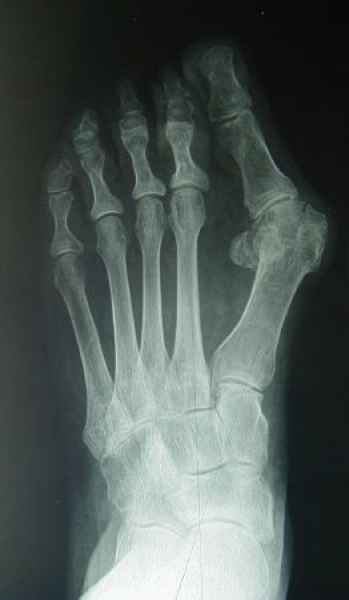

El pie es el órgano distintivo y característico de la especie humana, la única criatura que marcha erguida. El pie es una muy compleja estructura de arquitectura perfecta, adaptado a su función de apoyo, traslación, salto, con una riquísima sensibilidad que le permite detectar las más leves imperfecciones del suelo para estabilizar la marcha.

La marcha no solo es característica de la especie humana sino también de cada persona, y más aún varía según el estado de ánimo del momento. Una patología en los pies, se traduce en el rostro, en el ánimo, en el psiquismo. No sólo el dolor produce estos efectos, también un pie deformado o poco estético. En nuestra sociedad, la estética constituye un valor muy apreciado y estas alteraciones causan vergüenza fundamentalmente en las mujeres, que esconden en la playa sus pies en la arena y no pueden usar calzados elegantes.

Tanto la estructura del pie como su funcionalismo que es la marcha, pueden ser asiento y manifestación respectivamente de alteraciones locales ó sistémicas, por lo que su cuidadoso examen resulta de extrema utilidad diagnóstica.